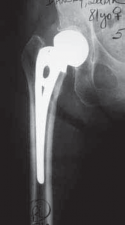

DEFINITION A fluted stem can be used to revise a loose femoral implant with one or more of the following: Cav…